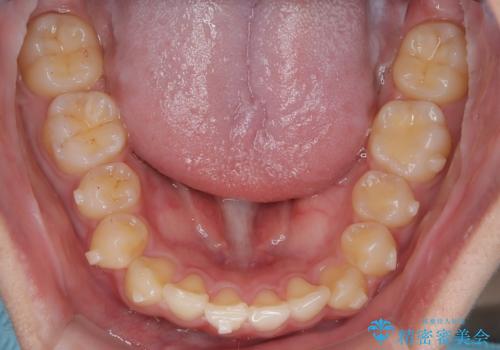

マウスピース矯正で前歯のガタツキを改善! 短期間で治療完了

- 前歯のガタツキが気になるとのことで来院されました。

マウスピース矯正で治療することとしました。